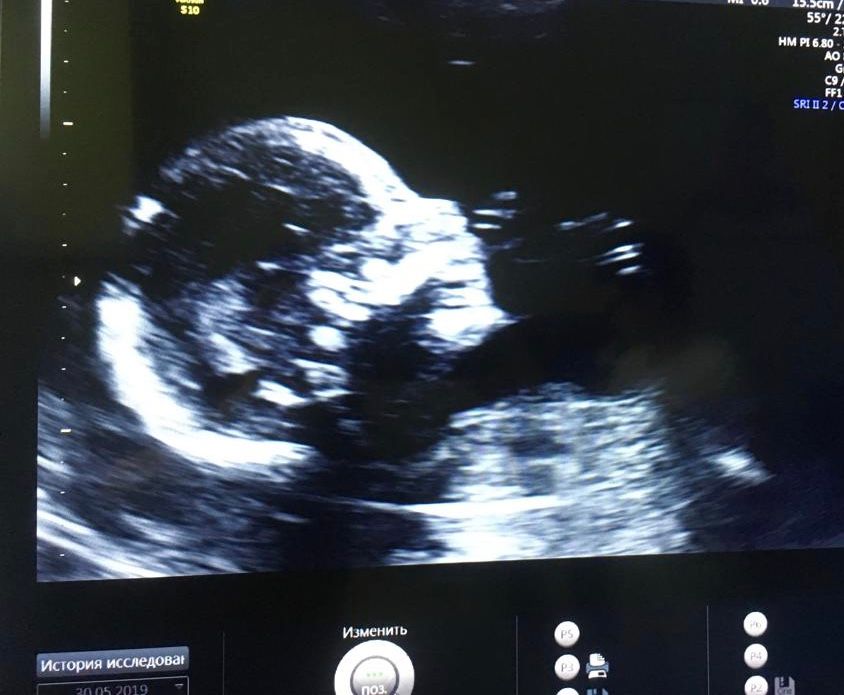

Мне кажется мальчик, у девочек головки более аккуратные

09.01.2022

Половой бугорок не видно на фото, но по очертанию профиля предположу мальчика - лобик выразительный, у девочек чаще всего он более сглажен. Но это так, из серии "погадать")

А мне кажется на девочку похоже, как будто параллельно все таки бугорок, а не 30⁰))) конечно ракурс не очень удобный)

Видно плохо,но похоже на мальчика 🐣

Я бы сказала, мальчик🤗